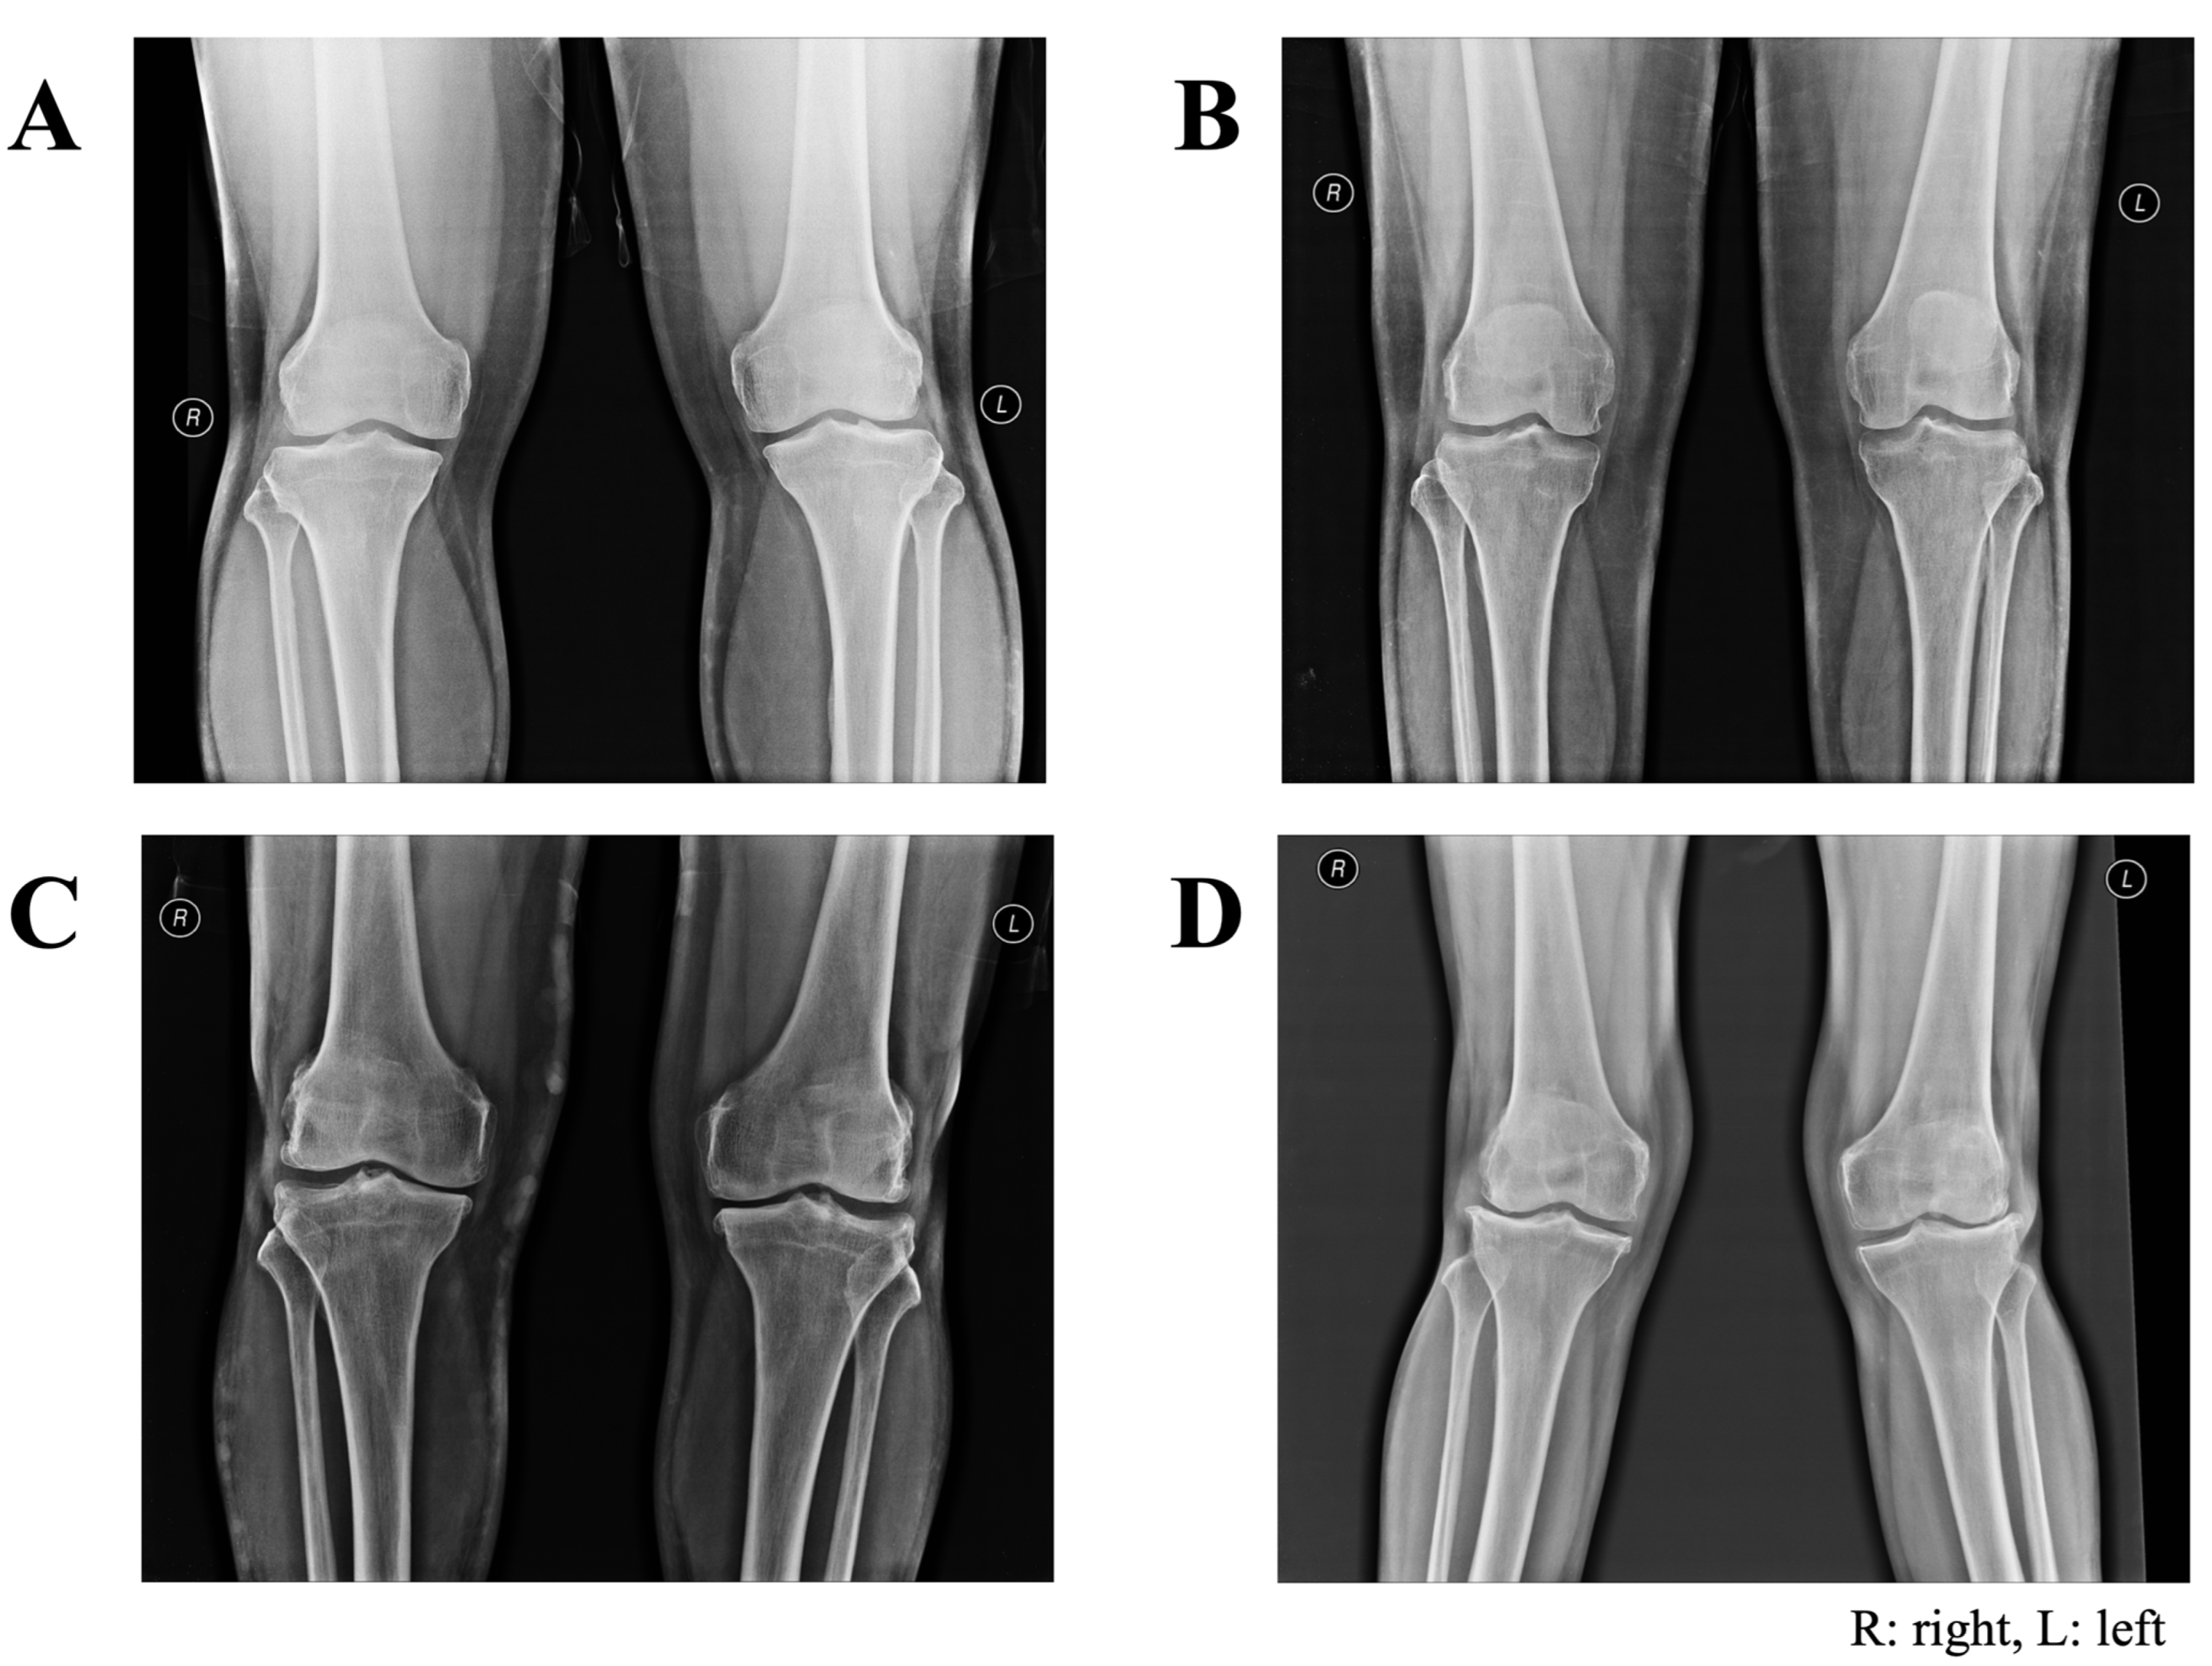

3.3. Frequency of Kellgren and Lawrence (KL) Grades for Pairs of Knees

All participants underwent radiographic examination of the bilateral knees using AP and lateral views with weight-bearing. Figure 3 shows sample images of knee joints classified as KL grade 0 to 3 in this study. All 83 controls were classified as bilateral KL grade 0. Among the 117 cases of symptomatic knee OA, 115 were diagnosed with clinical and radiographic changes, and two were diagnosed as early knee OA with clinical relevance only concerning both knees (bilateral KL grade 0). Table 6 shows the frequencies of KL grades for the left and right knees in the case group. Based on the most observed radiographic changes, 58 OA knees (49.6%, 95% CI 40.2–58.9) were classified as bilateral KL grade 1. Among the others, 23 cases (19.7%, 95% CI 12.9–28.0) were classified as bilateral KL grade 2, 13 cases (11.1%, 95%CI 6.1–18.3) as unilateral KL grade 1, six cases (5.1%, 95%CI 1.9–10.8) as unilateral KL grade 2, and five cases (4.3%, 95%CI 1.4–9.7) as bilateral KL grade 3. However, unilateral or bilateral KL grade 4 was not found in this study.

Figure 3.

Examples of anteroposterior radiographs of paired knees presented in the current study: (A) bilateral KL grade 0, demonstrating normal bone density and good alignment; (B) bilateral KL grade 1, demonstrating possible joint space narrowing with small osteophytes in right knee; (C) bilateral KL grade 2, demonstrating narrow knees and patellofemoral joints with spur; (D) bilateral KL grade 3, demonstrating mild genu varus deformity with no displaced fracture, subchondral sclerosis with joint space narrowing, and osteophyte formation in lateral tibiofemoral joint space.

Frequency of KL grades using paired knee radiographs of 117 participants with symptomatic knee OA.